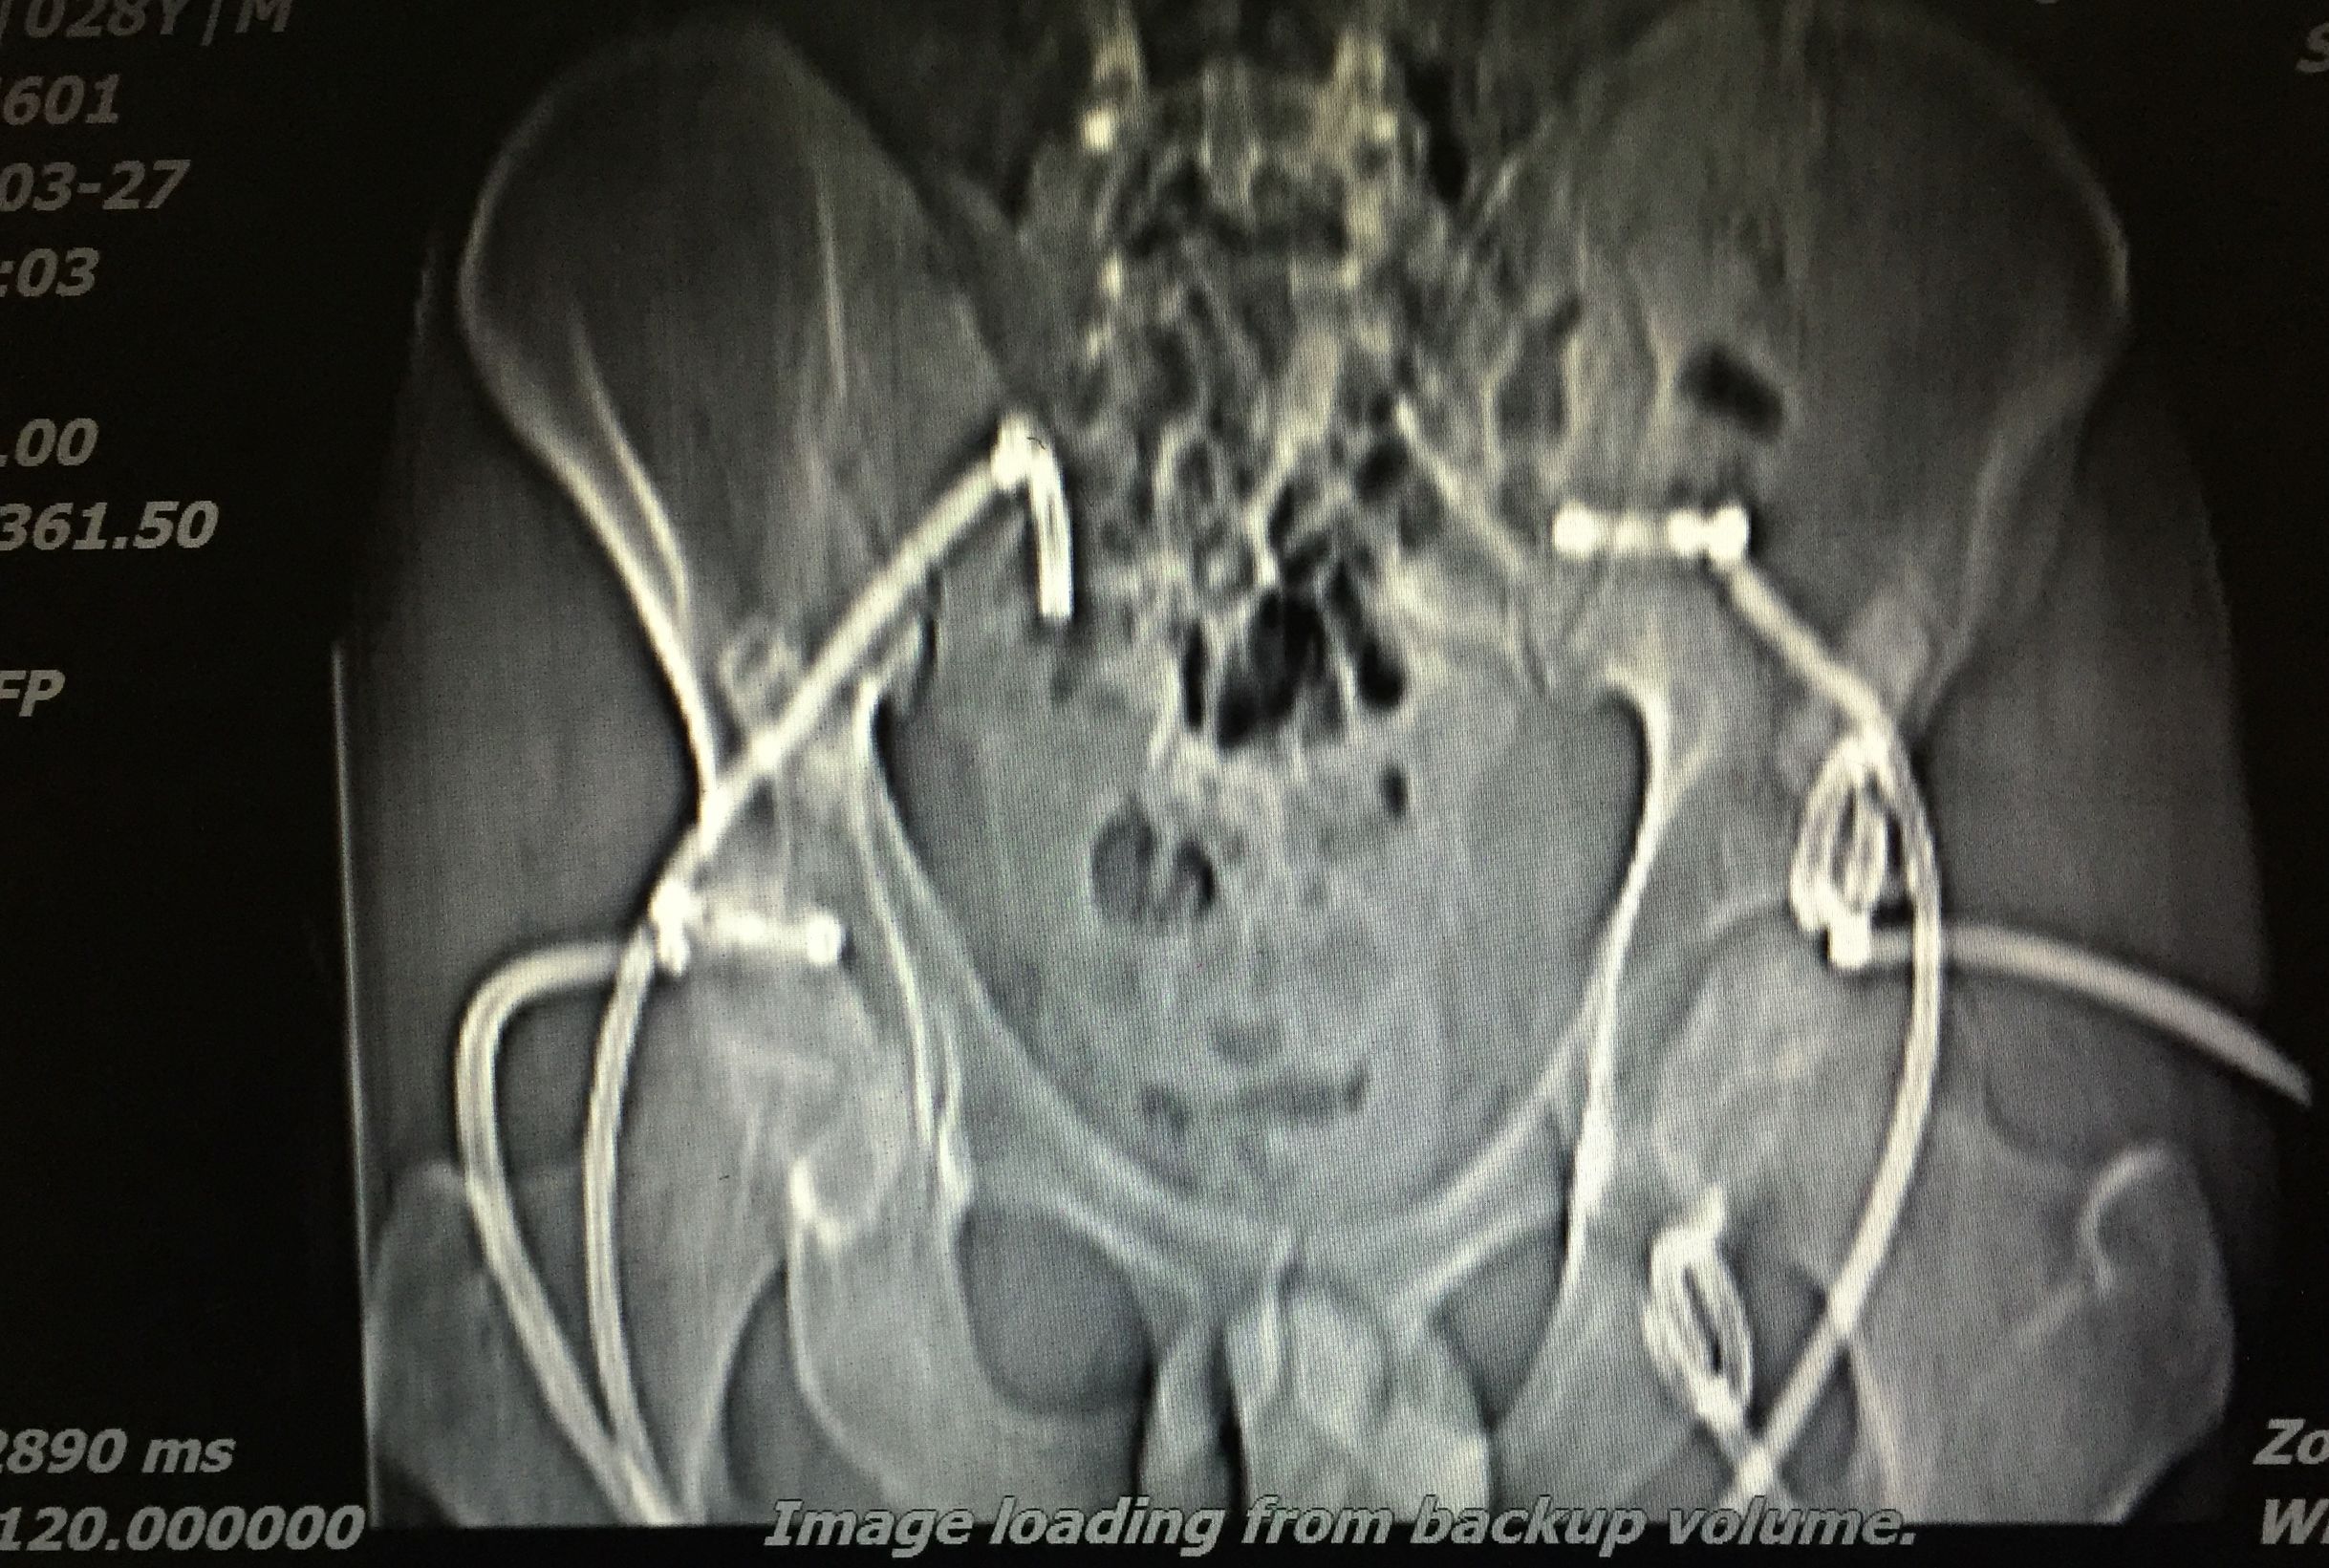

患者 20岁,低热、盗汗半年余,腰骶部疼痛。CT显示盆腔多发结核脓肿,同时骶骨骨质基本破坏,骨盆力学结构受损。

我们对患者在门诊进行充份置管引流(白色条状物5根)

在患者持续引流状态下,并联合抗痨治疗。如下图所示,脓肿完全吸收。患者痊愈。